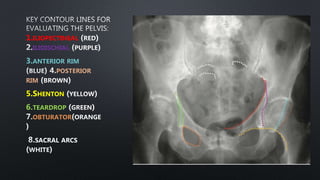

LINES

1.ILIOPECTINEAL

ILIOISCHIAL

3.ANTERIOR RIM

POSTERIOR

RIM

5.SHENTON

6.TEARDROP

OBTURATOR

SACRAL ARCS